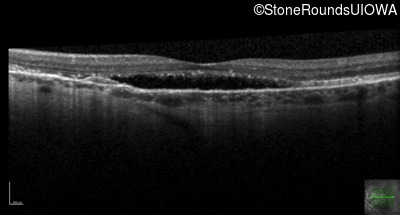

Age at visit: 58 years